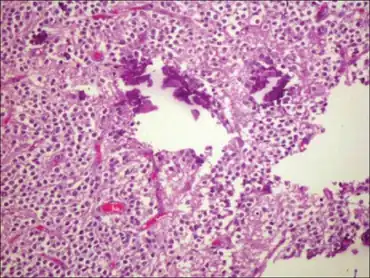

H and E staining showing histological features of neurocytoma